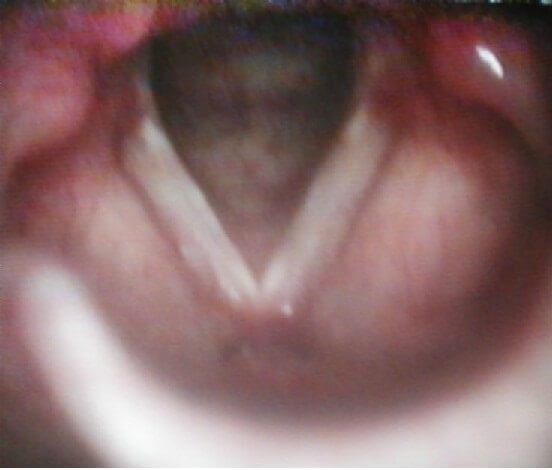

При дыхании край голосовой складки был ровный, хорошо натянут. Во время фонации они колебались регулярно, симметрично, с малой амплитудой. Фаза контакта укорочена (рис.2).